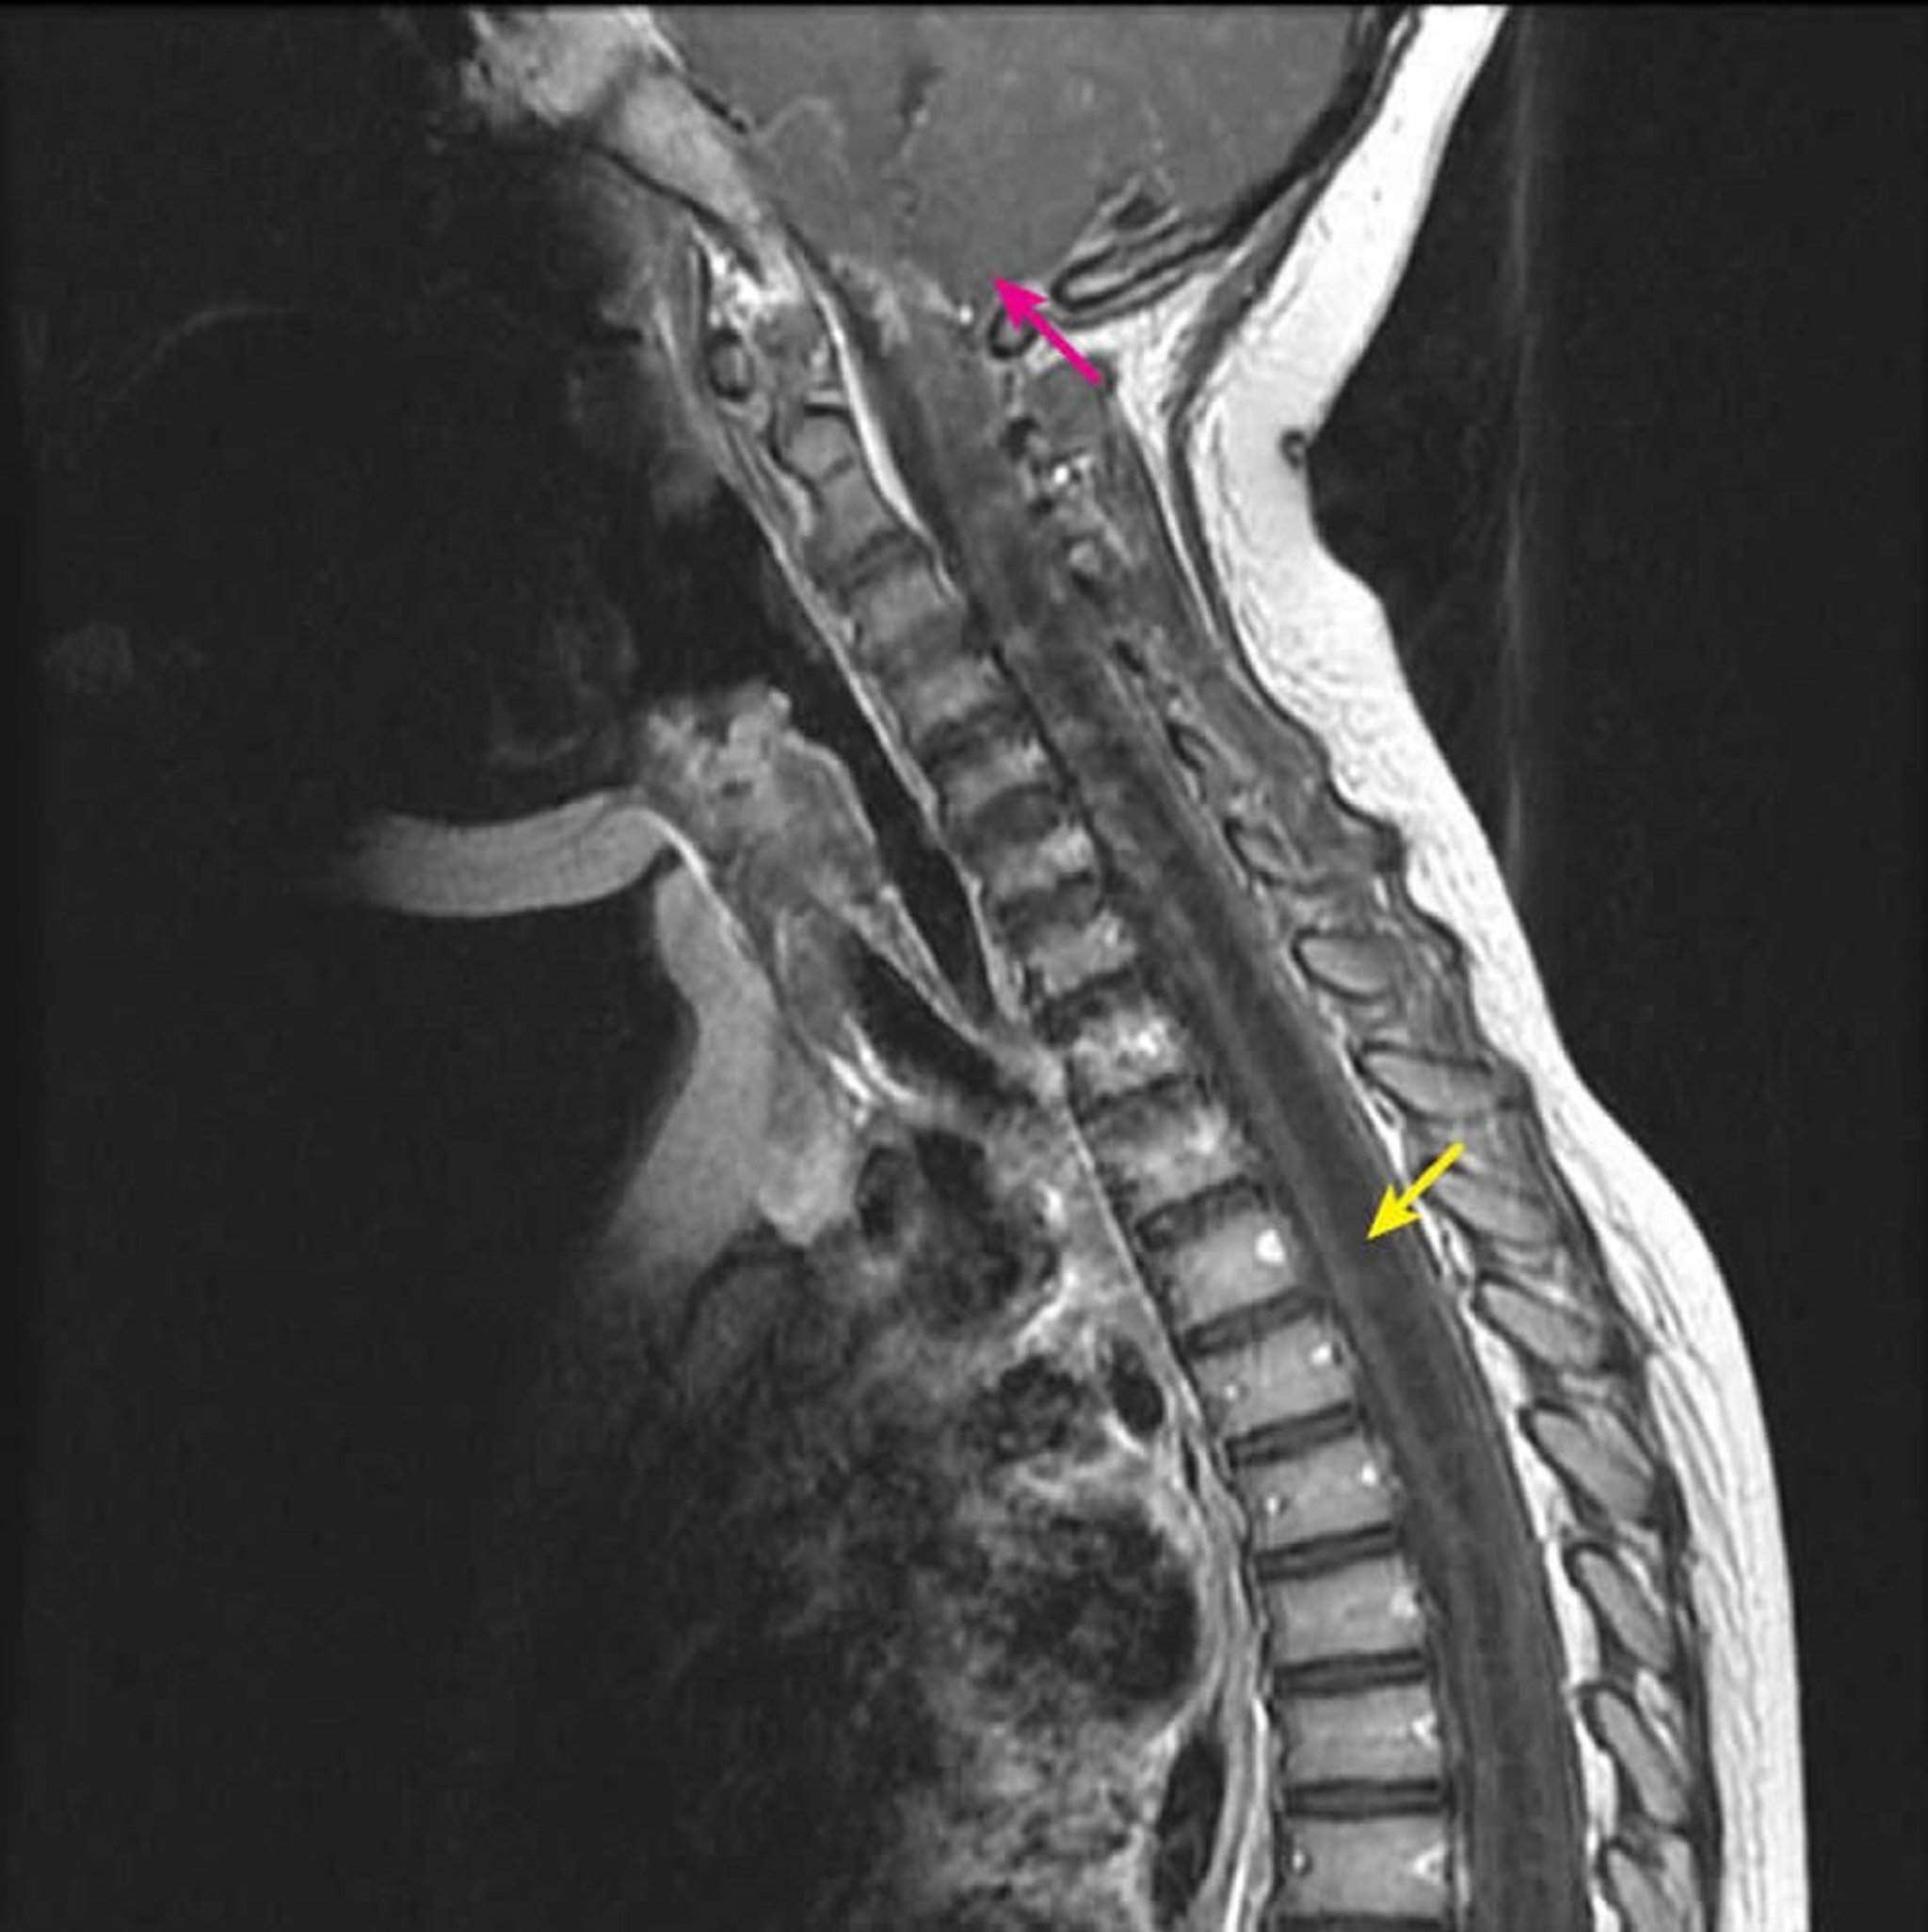

Syringohydromyélie cervicothoracique

L'IRM sagittale post-contraste pondérée en T1 montre une grande cavité intramédullaire hypo-intense en T1 caractéristique d'une syrinx (flèche jaune). Elle s'étend du niveau cervical C2-C3 vers le bas chez un enfant atteint d'une malformation de Chiari I connue (flèche rose). Ce signe est défini comme une syringohydromyélie parce que la syringomyélie (une cavité excentrique de la moelle épinière) ne peut être différenciée de l'hydromyélie (une cavité médullaire centrale) par l'imagerie.